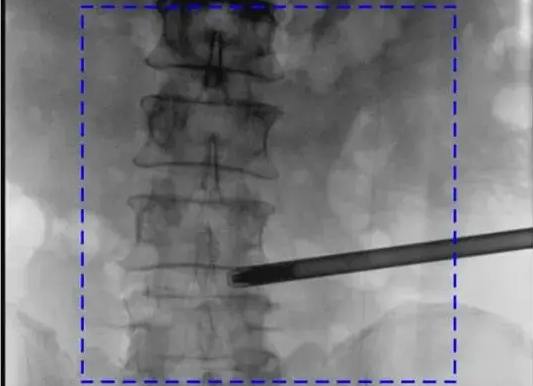

三維C形臂與二維C形臂臨床圖像實時對比

移動式C形臂X射線機有著二維和三維之分,它們都具備透視與攝影功能,能夠為醫生提供術中影像引導。三維C形臂采集的圖像究竟比二維C形臂好在哪?下面我們結合臨床病例的影像來解答!...